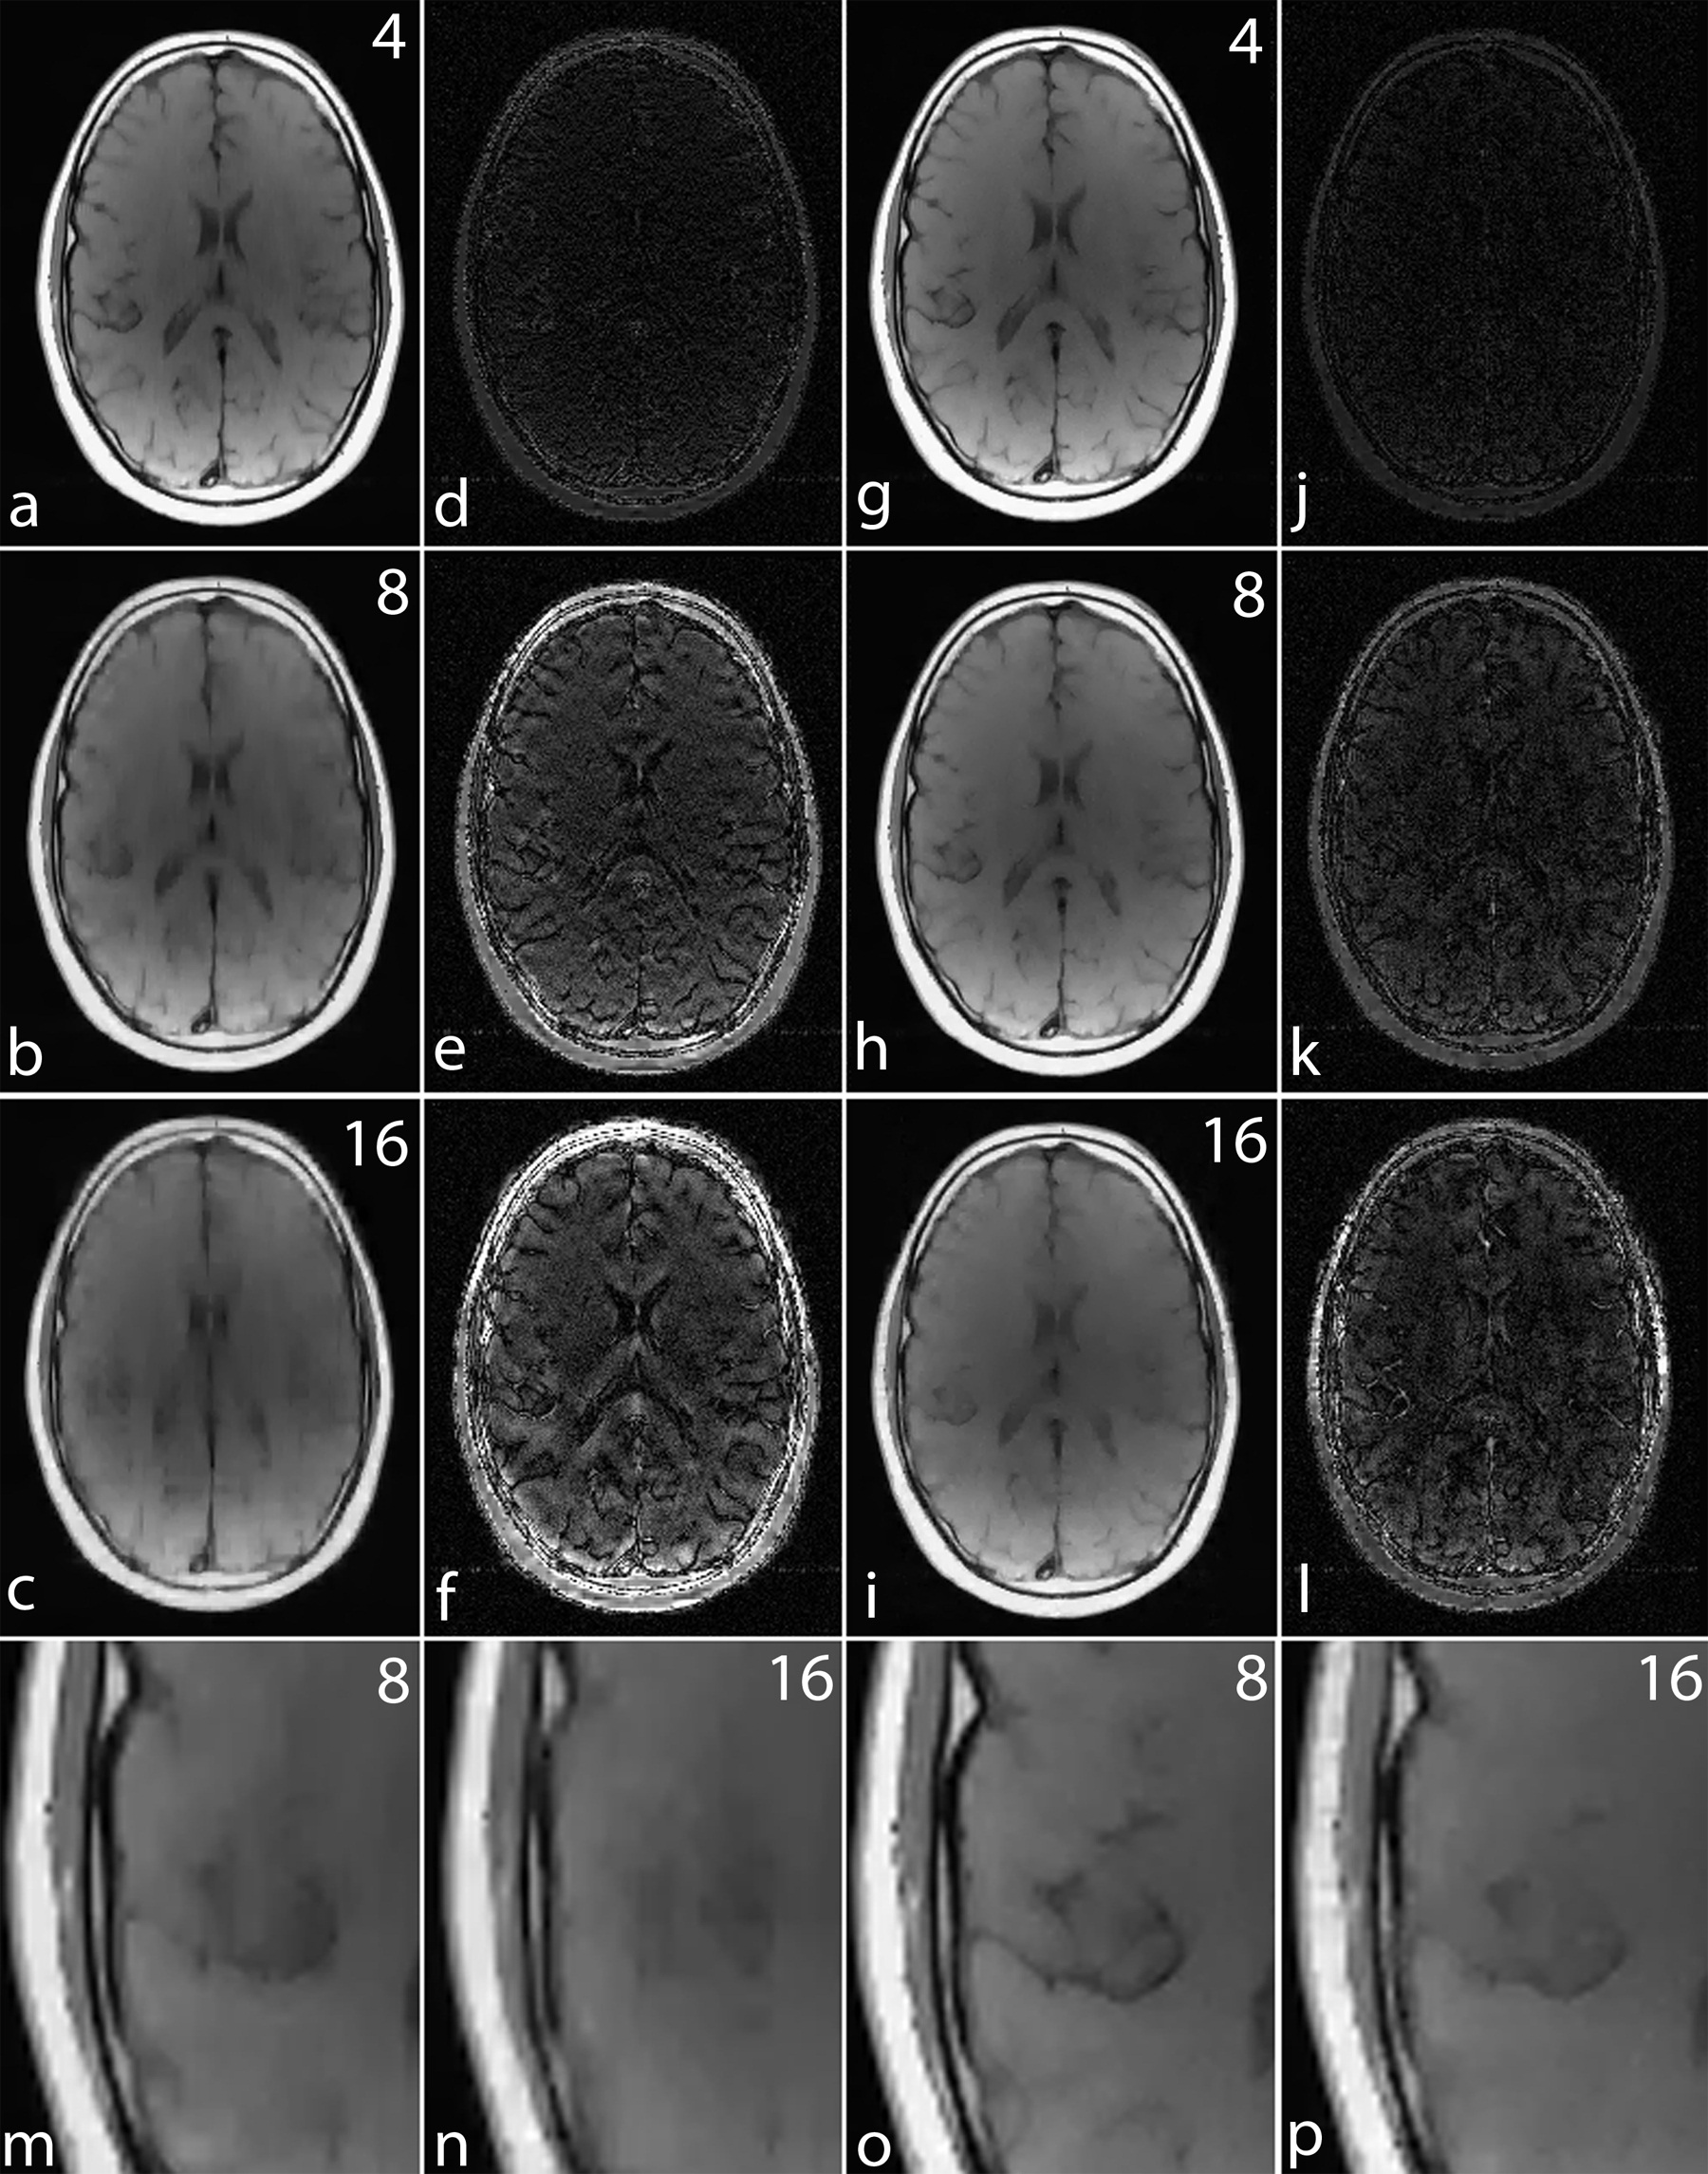

For a noiseless simulation, the reconstructed images for different acceleration factors (4, 8 and 16) are shown in Fig. 8. The difference images in Fig. 8 (d)-(f) and (j)-(l) demonstrate that the error in noiselet encoding is always less than in Fourier encoding, and that the noiselet encoded MCS-MRI reconstruction preserves spatial resolution better than the Fourier encoded MCS-MRI. Fig. 8 (m) and (n) show the zoomed images reconstructed with Fourier encoding for acceleration factors of 8 and 16 respectively, while Fig. 8 (o) and (p) show the zoomed images reconstructed with noiselet encoding for an acceleration factors of 8 and 16 respectively. The zoomed images highlight that the spatial resolution of the noiselet encoded reconstructions outperforms the Fourier encoded reconstructions. Moreover, the spatial resolution provided by the noiselet encoding at an acceleration factor of 16 is comparable to that of the Fourier encoding at an acceleration factor of 8, suggesting that noiselet encoding performs approximately twice as good as Fourier encoding.

To validate the feasibility of the proposed reconstruction method, we performed retrospective under-sampling on the acquired noiselet encoded data and Fourier encoded data to simulate accelerated data acquisition. After retrospective under-sampling, the unconstrained optimization program (10) was solved using the non-linear conjugate gradient method to reconstruct the desired image for different acceleration factors. Fig. 12 (a)-(c) shows the reconstructed images for the acceleration factors of 4, 8 and 16 on the Fourier encoded data while Fig. 12 (d)-(f) shows the corresponding difference images. Similarly, Fig. 12 (g)-(i) shows the reconstructed images for the acceleration factors of 4, 8 and 16 on the noiselet encoded data, and Fig. 12 (j)-(l) shows the corresponding difference images for noiselet encoded MCS-MRI. These results on the acquired data are consistent with the simulation results and indicate that the noiselet encoding is superior to the Fourier encoding in preserving resolution.

Fig. 12 (A-H) shows the zoomed portion of the reconstructed images with Fourier encoding and noiselet encoding. One can distinguish between the small dots in the zoomed images reconstructed with noiselet encoding while it is difficult to distinguish these dots in the images reconstructed with Fourier encoding. This demonstrates that noiselet encoding is able to preserve resolution better than the Fourier encoding. Fig. 13 show the images reconstructed with Fourier encoding and noiselet encoding for various acceleration factors on the data acquired for one axial slice of the brain. Since the SNR of the in vivo images is less than in the phantom images, reconstruction is shown only up to an acceleration factor of 8. The difference images demonstrate that noiselet encoding outperforms Fourier encoding for all acceleration factors. In particular, at the acceleration factor of 8 the image reconstructed with Fourier encoded data has significantly poorer resolution compared to the image reconstructed with noiselet encoded data.